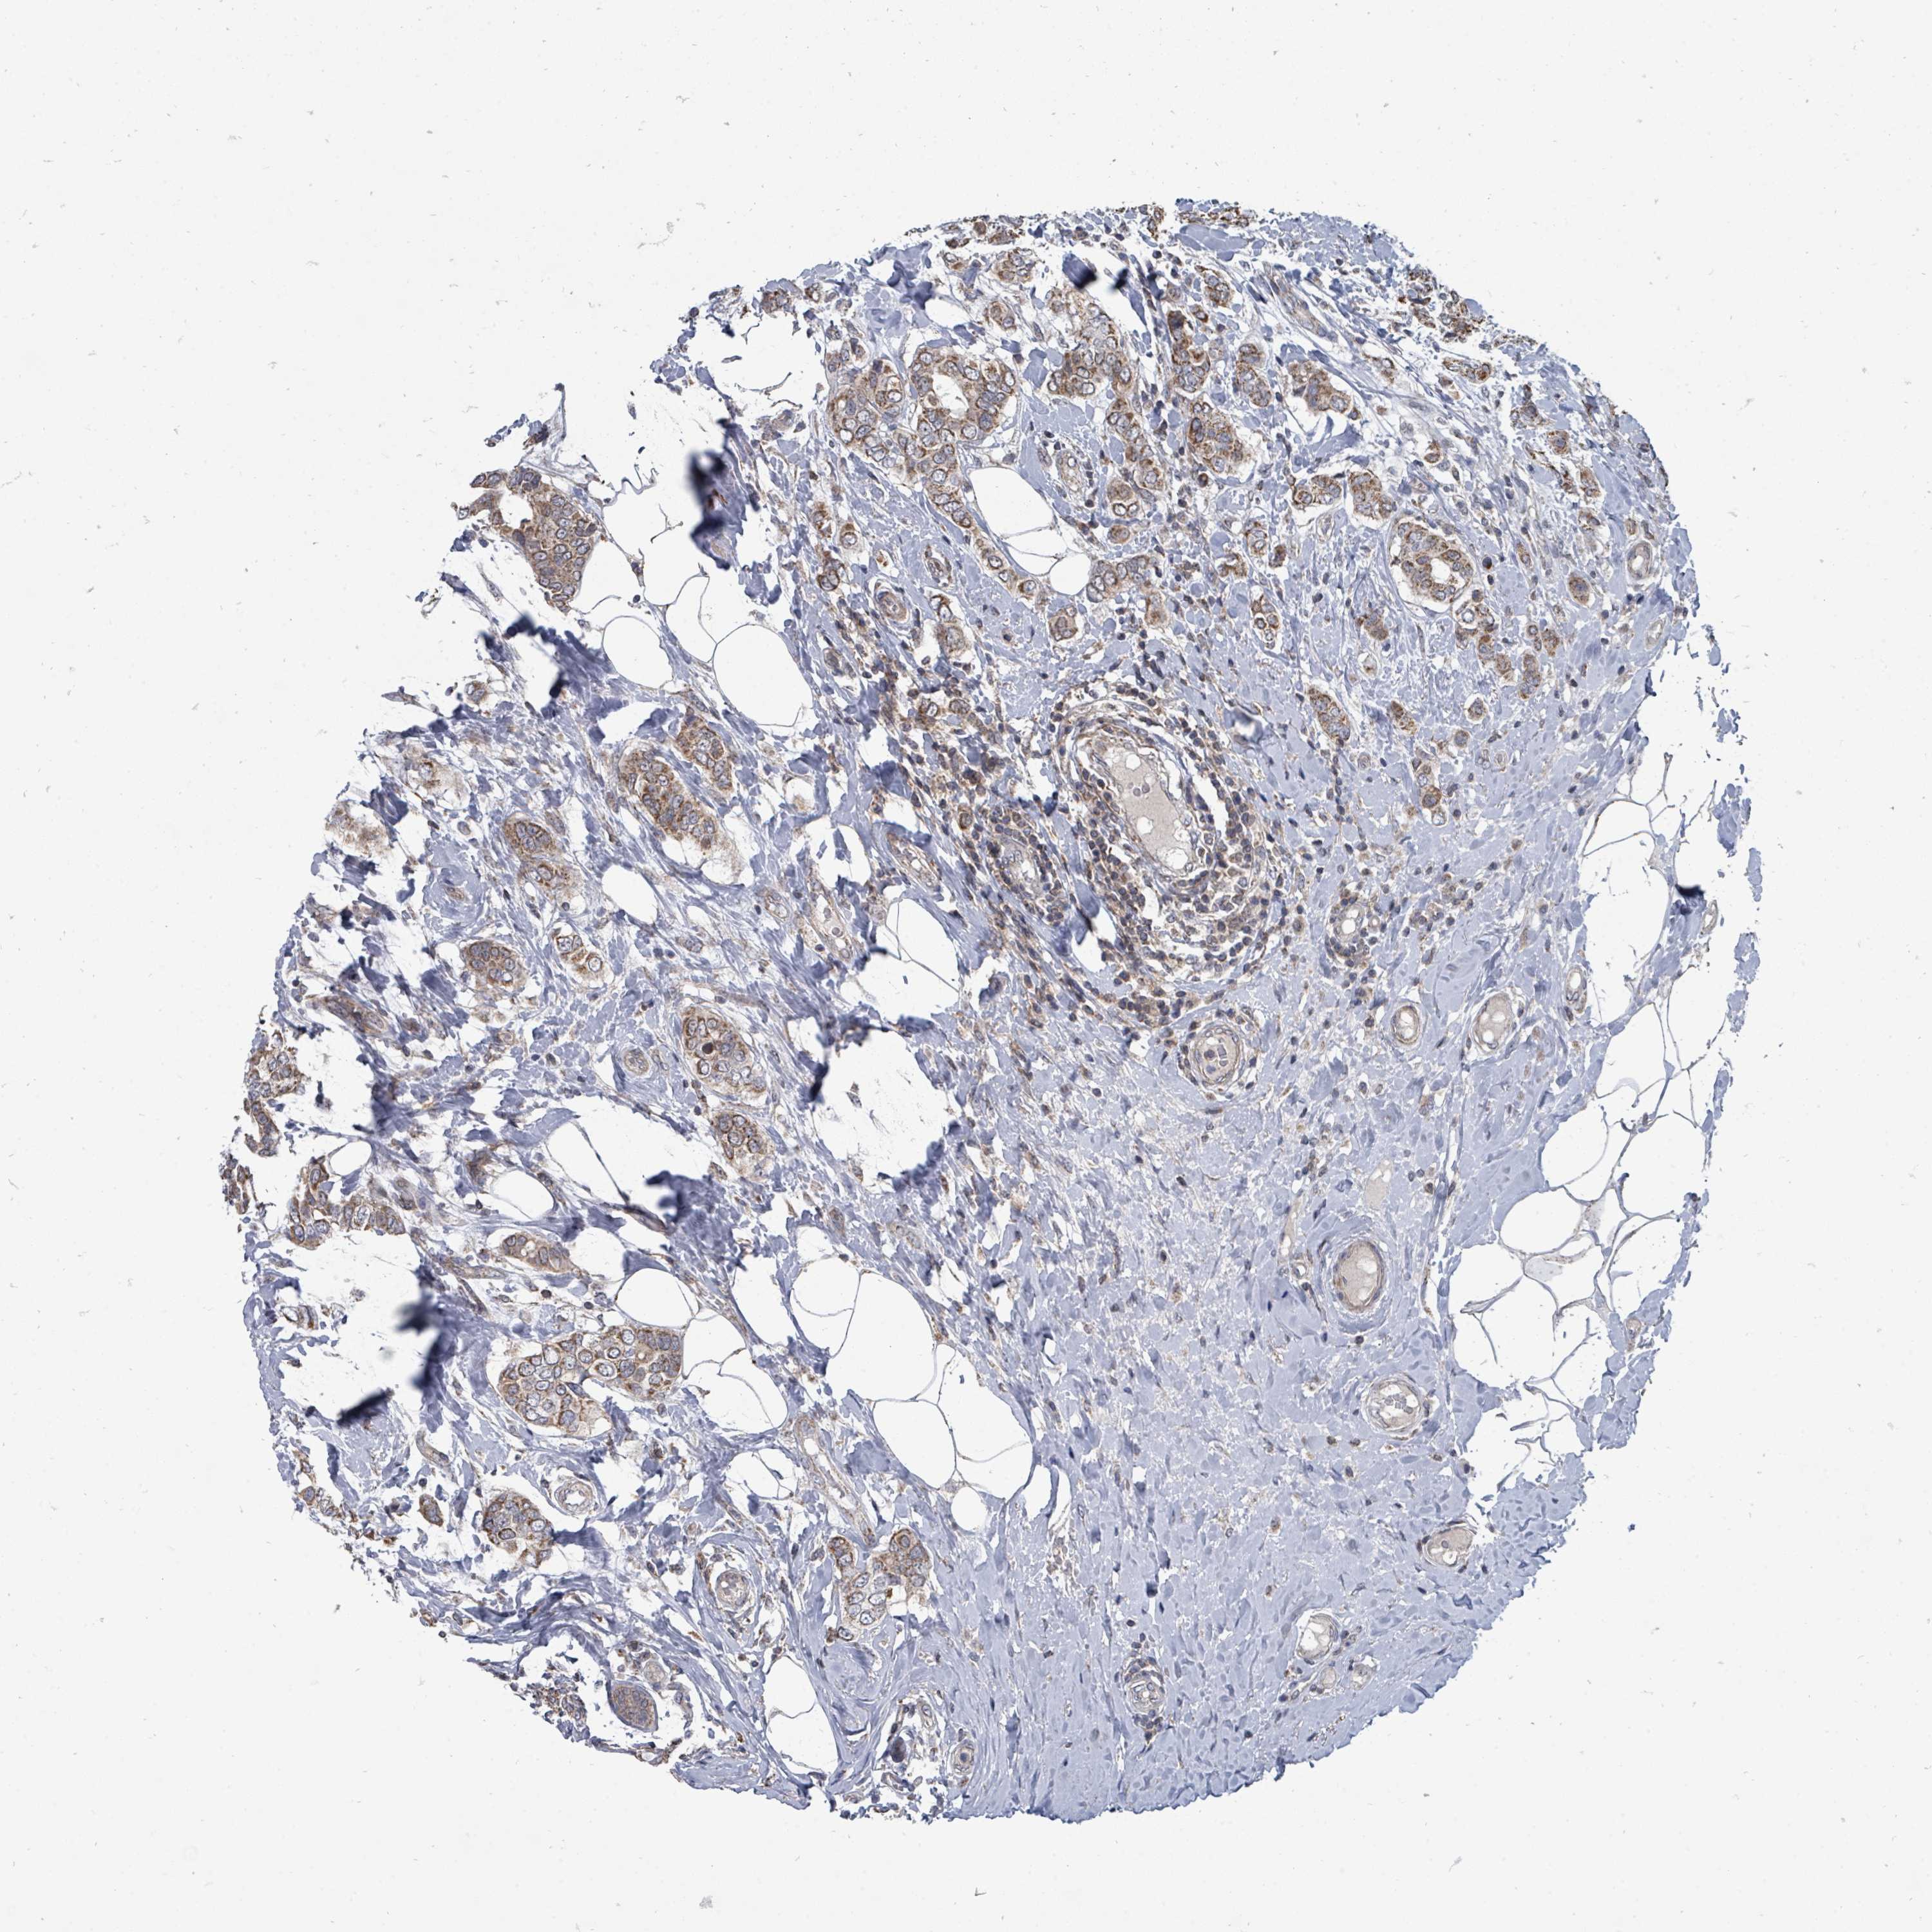

CANCER BREAST CANCER Show tissue menu

BRCA TCGA BRCA VALIDATION PROTEIN EXPRESSION